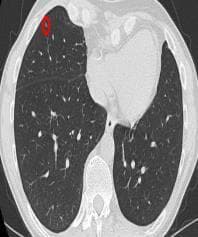

These leaderboards are used to track progress in lung-nodule-segmentation-3

It is shown that iW-Net allows to correct the segmentation of small nodules, essential for proper patient referral decision, as well as improve the segmentations of the challenging non-solid nodules and thus may be an important tool for increasing the early diagnosis of lung cancer.

A 3D probabilistic segmentation framework augmented with NFs, to enable capturing the distributions of various complexity, and is the first to present a 3D Squared Generalized Energy Distance (D2 GED) of 0.401 and a high 0.468 Hungarian-matched 3D IoU.